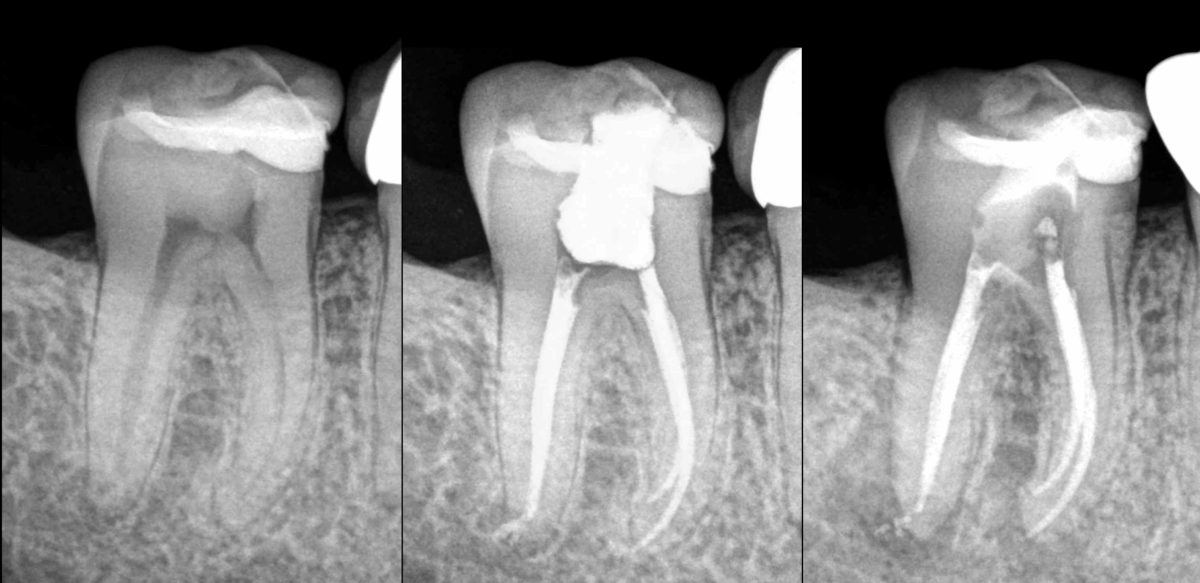

🦷 𝐍𝐞́𝐜𝐫𝐨𝐬𝐞 𝐩𝐮𝐥𝐩𝐚𝐢𝐫𝐞, 𝐩𝐚𝐫𝐨𝐝𝐨𝐧𝐭𝐢𝐭𝐞 𝐚𝐩𝐢𝐜𝐚𝐥𝐞 𝐬𝐲𝐦𝐩𝐭𝐨𝐦𝐚𝐭𝐢𝐪𝐮𝐞 (lésion apicale racine D).

➡️ 𝐈𝐧𝐝𝐢𝐜𝐚𝐭𝐢𝐨𝐧 𝐝𝐞 𝐭𝐫𝐚𝐢𝐭𝐞𝐦𝐞𝐧𝐭 𝐜𝐚𝐧𝐚𝐥𝐚𝐢𝐫𝐞.

📆 À 1 an, le traitement montre qu’il n’est pas suffisamment efficace pour permettre la 𝐜𝐢𝐜𝐚𝐭𝐫𝐢𝐬𝐚𝐭𝐢𝐨𝐧 𝐨𝐬𝐬𝐞𝐮𝐬𝐞 𝐞𝐧 𝐝𝐢𝐬𝐭𝐚𝐥 (évolution de la lésion osseuse).

Parce que l’𝐚𝐧𝐚𝐭𝐨𝐦𝐢𝐞 𝐜𝐚𝐧𝐚𝐥𝐚𝐢𝐫𝐞 est bien plus complexe qu’elle n’apparaît sur les radios : 𝐜𝐚𝐧𝐚𝐮𝐱 𝐚𝐜𝐜𝐞𝐬𝐬𝐨𝐢𝐫𝐞𝐬, 𝐜𝐚𝐧𝐚𝐮𝐱 𝐥𝐚𝐭𝐞́𝐫𝐚𝐮𝐱, 𝐢𝐬𝐭𝐡𝐦𝐞, formes canalaires non rondes… 😵💫